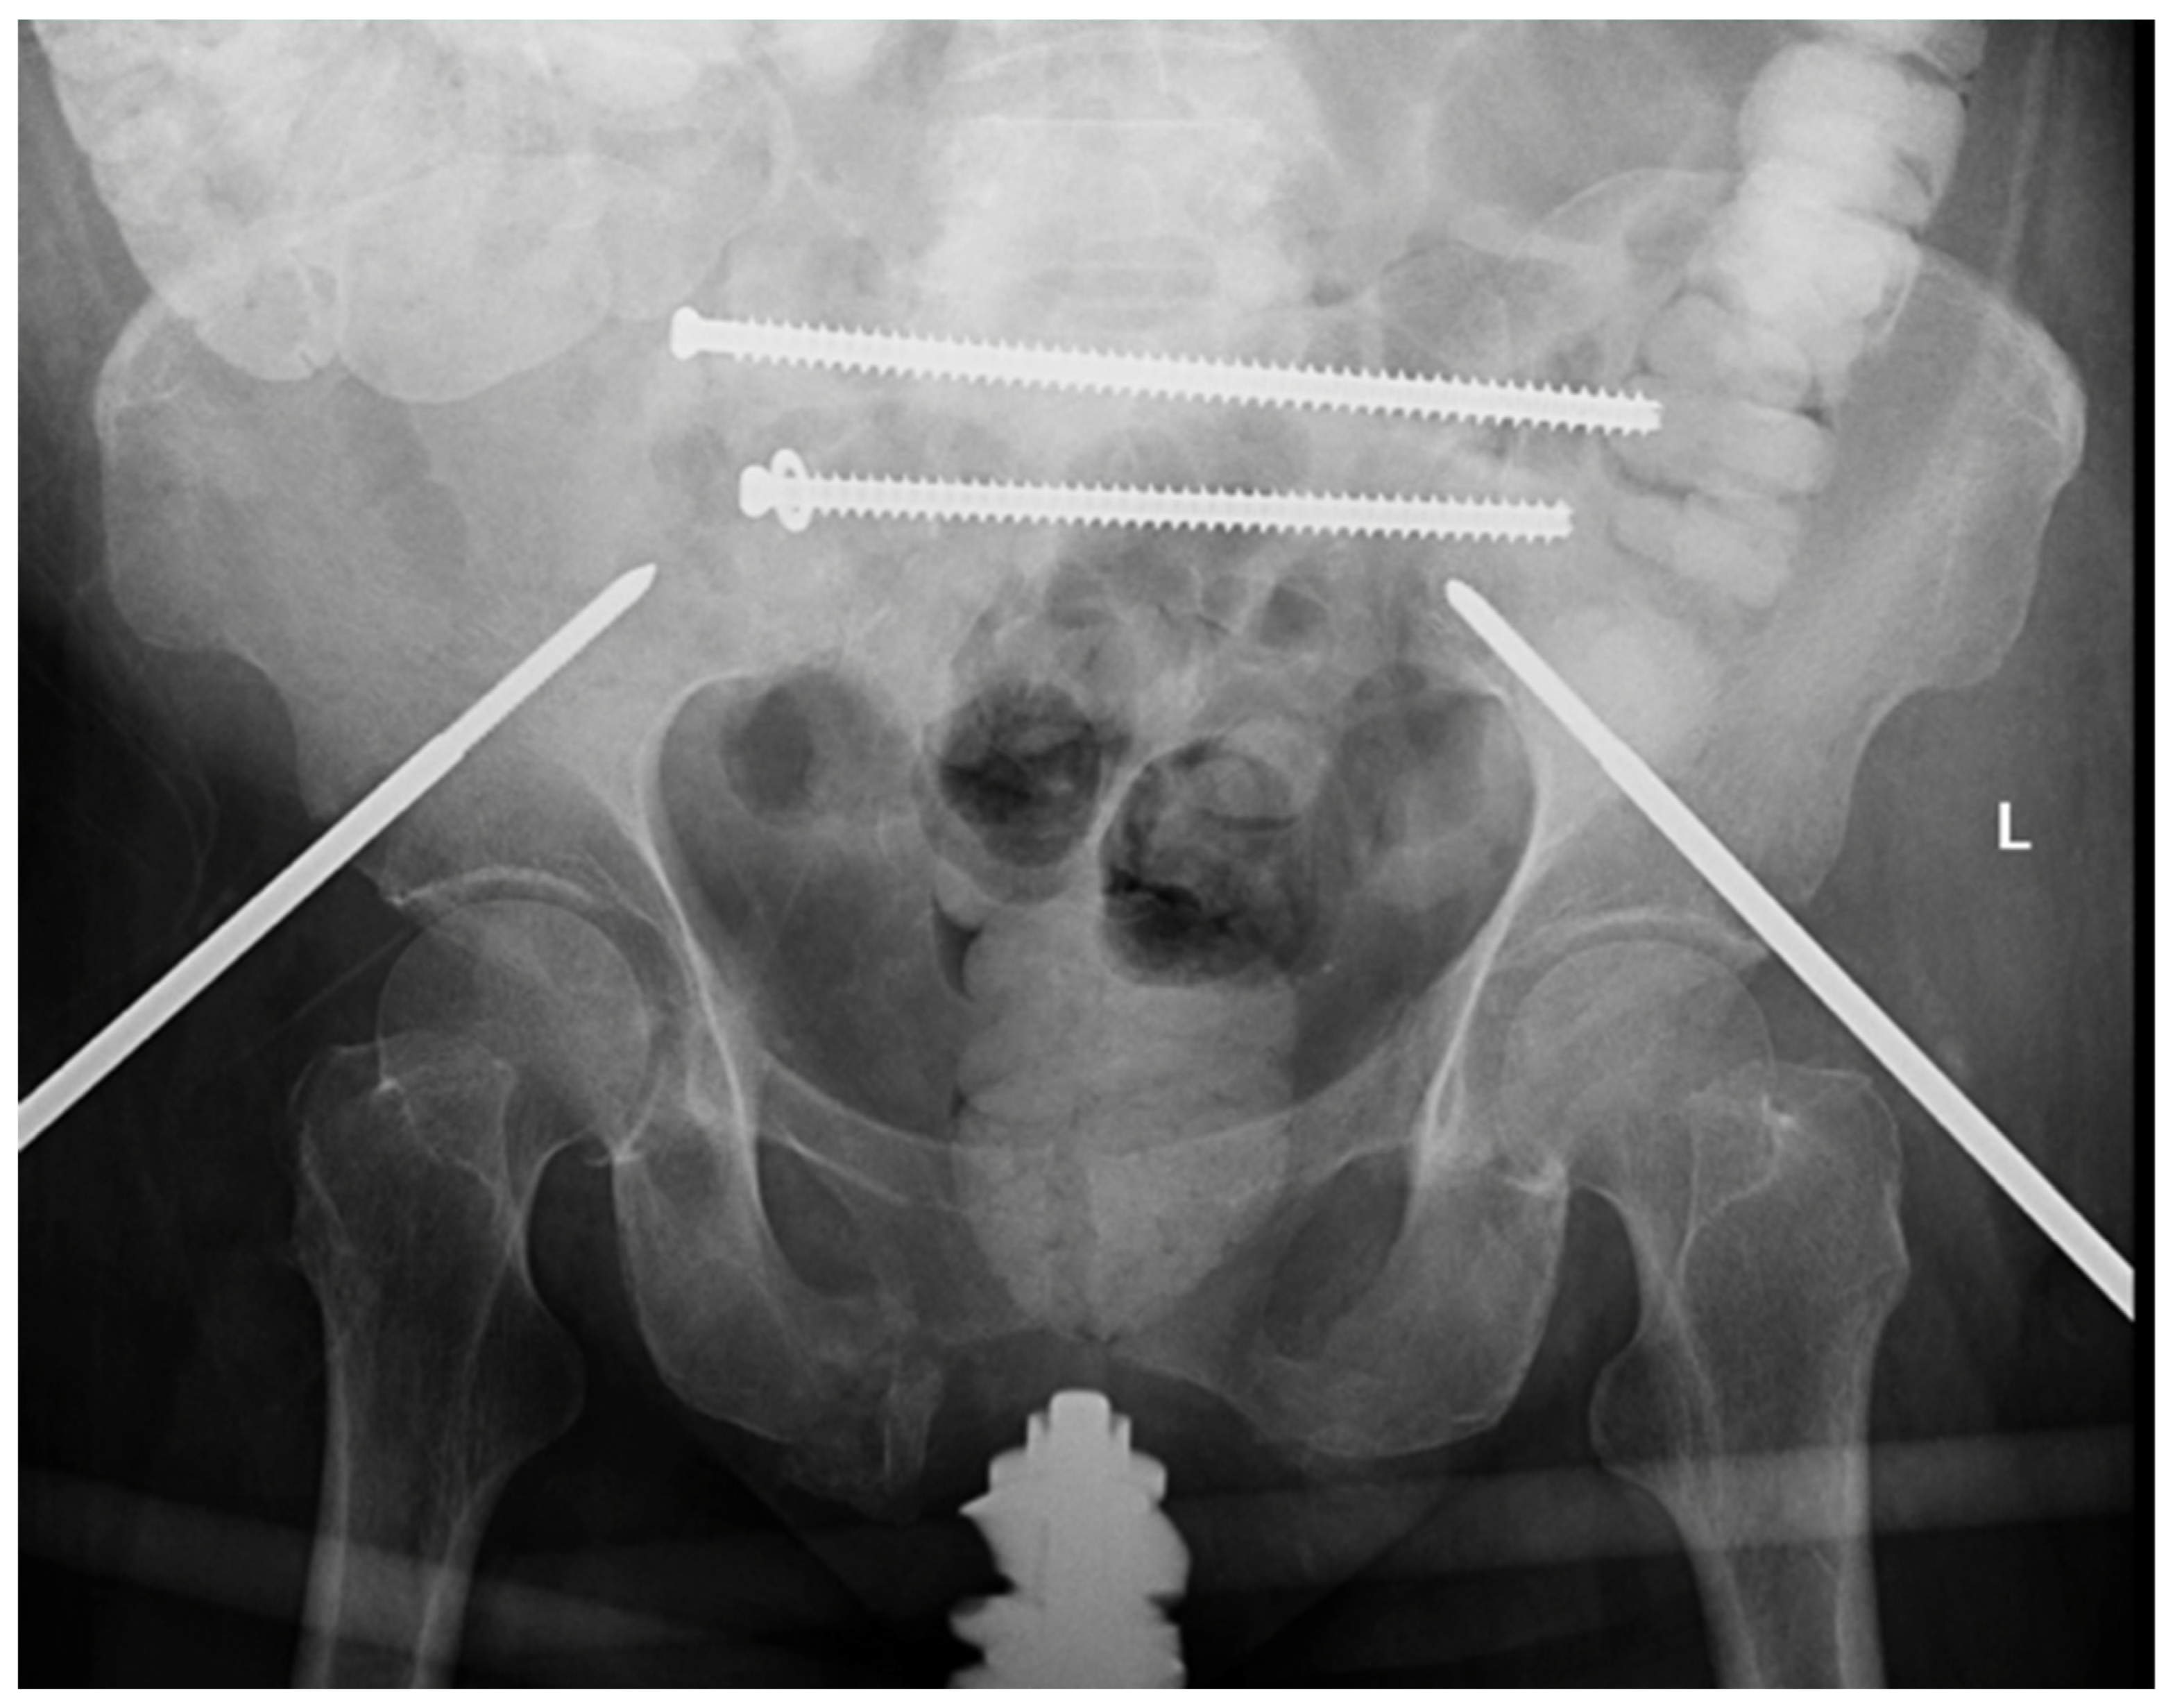

The patient was then repositioned to a supine position to address the bilateral superior and inferior pubic rami fractures. The anterior pelvis had been partially reduced due to the posterior stabilization in the sacrum. Interim packing from multiple prior abdominal surgeries had rendered external fixation as the most appropriate treatment. Five mm Schanz pins were placed along the LC-2 corridor in typical fashion to create a Hannover frame (Figure 3). After appropriate positioning was confirmed via fluoroscopy, pins were connected via external fixator bars and clamps. There were no obvious perioperative complications, and the patient was transferred to the post-anesthesia care unit (PACU).

Figure 3.

AP pelvis demonstrating placement of 5 mm Schanz pins were along LC-2 corridor in typical fashion to create Hannover external fixation frame as well as demonstrating placement of trans-iliac trans-sacral screws at S1 and S2 levels.